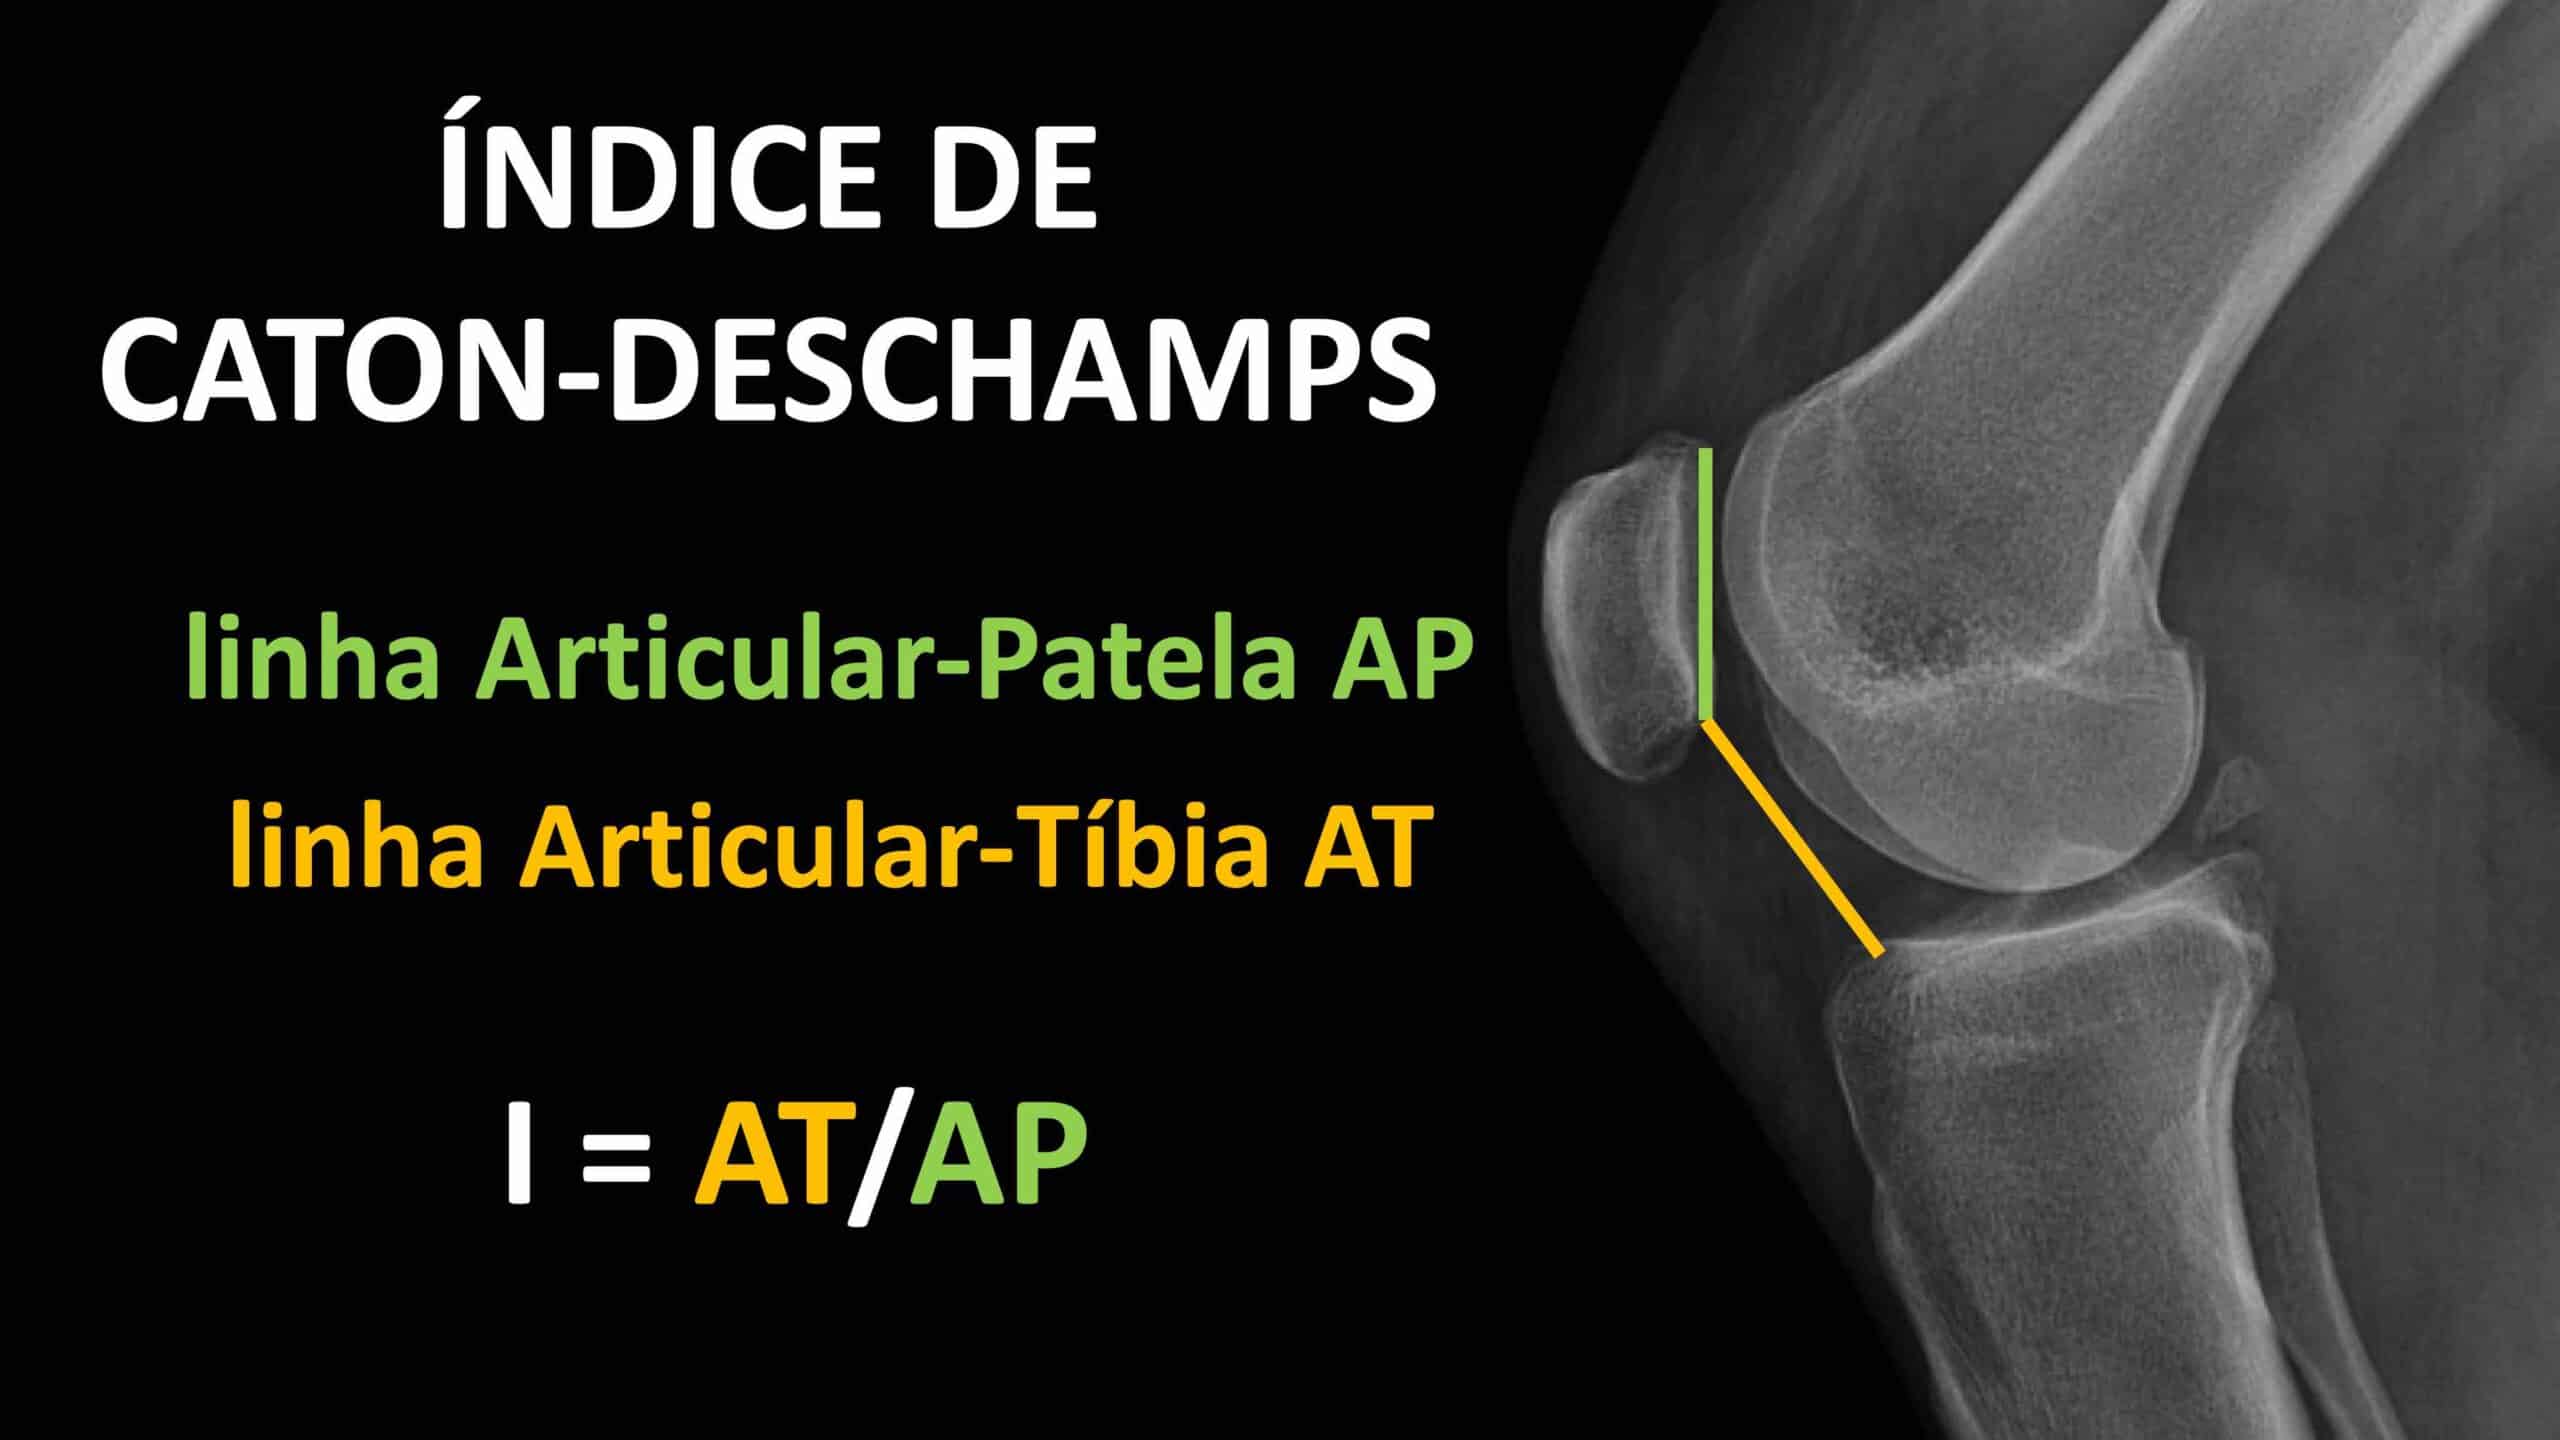

Diferente de outros métodos, o Índice de Caton-Deschamps utiliza pontos de referência articulares, o que o torna aplicável mesmo se a ponta da patela estiver quebrada ou se houver uma deformidade na base. A medida deve ser feita preferencialmente em uma radiografia de perfil do joelho, com a articulação estando fletida cerca de 30 graus. Com um lápis e uma régua, traçam-se duas linhas: uma delas é a medida da superfície articular da patela ( linha AP ou Articular-Patela ) e a outra linha é a linha AT ( ou Articular-Tíbia ), que é a distância do ponto mais inferior da superfície articular da patela até o ângulo anterossuperior do platô tibial. A fórmula do Índice de Caton-Deschamps é a razão entre a linha AT pela linha AP. Após realizar o cálculo, o valor obtido pode ser classificado da seguinte maneira: de 0,6 a 1,2 a altura da patela é considerada normal, abaixo de 0,6 a altura da patela é considerada baixa e acima de 1,2 a altura da patela é considerada alta. Um valor de 1,0 é considerado o equilíbrio perfeito, onde a superfície articular da patela é exatamente igual à sua distância até o platô tibial. O Índice de Caton-Deschamps também pode ser medido numa tomografia computadorizada do joelho usando o Protocolo de Lyon. A altura patelar é um dos 4 fatores descritos por Dejour de instabilidade da patela.